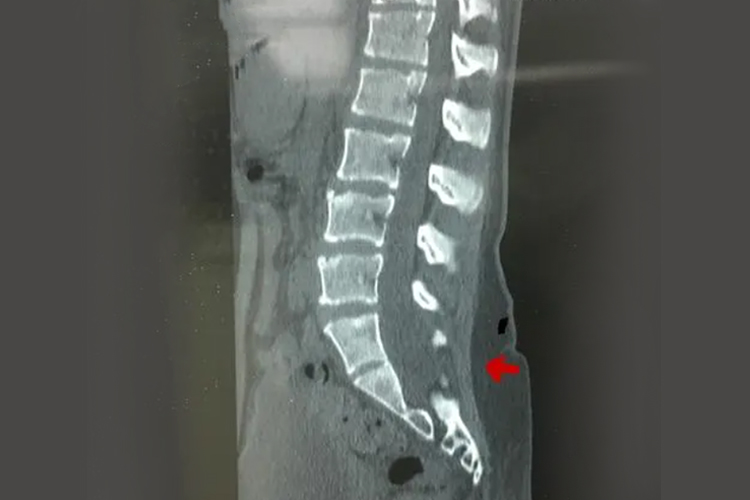

先天性隐性脊柱裂较难发现,常经影像学检查发现,是由棘突及椎板的先天性缺损导致。

先天性隐性脊柱裂是棘突及椎板的先天性缺损,如脊柱裂只是累及骨骼,即椎弓正中部愈合不全,同时脊膜和神经组织从该处脱出。患者通常没有不适症状,多是偶然检查时发现。